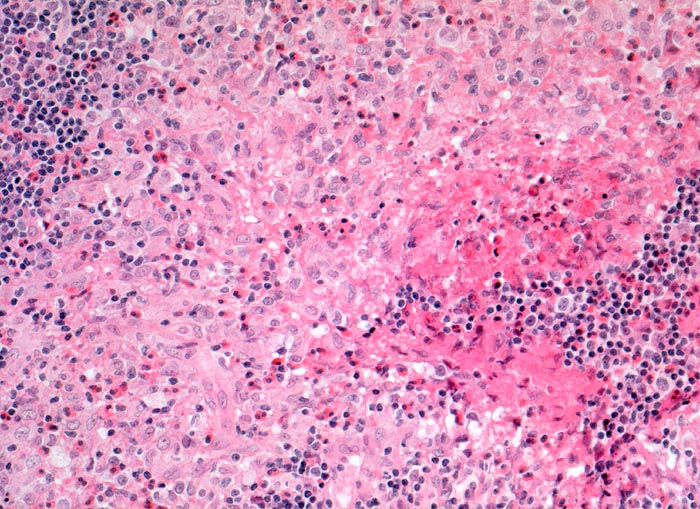

PathoPic – image database / PathoPic ID 3747 - Langerhanszell Histiozytose

Langerhanszell Histiozytose

Lymphknoten, Kopf-cervikal

Infiltratherd bestehend aus Langerhanszellen mit bohneförmigen Kernen und reichlich hellem Zytoplasma. Dazwischen zahlreiche eosinophile Granulozyten.

CD1a und S-100 positive Langerhanszellen in den hellen Infiltratherden